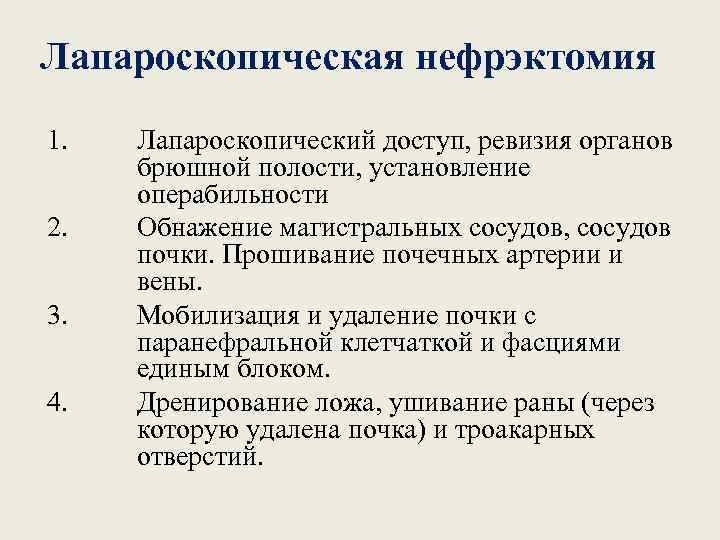

Лапароскопическая нефрэктомия 1. 2. 3. 4. Лапароскопический доступ, ревизия органов брюшной полости, установление операбильности Обнажение магистральных сосудов, сосудов почки. Прошивание почечных артерии и вены. Мобилизация и удаление почки с паранефральной клетчаткой и фасциями единым блоком. Дренирование ложа, ушивание раны (через которую удалена почка) и троакарных отверстий.